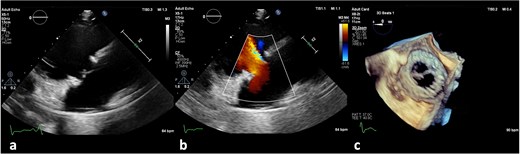

On the third day of hospitalization, transesophageal echocardiography revealed only moderate mitral regurgitation (Videos 3 and 4). However, on day 11, follow-up echocardiography showed a 7 × 18 mm vegetation on the prosthetic aortic valve, with a 5 × 7 mm floating formation (Fig. 2, Videos 5 and 6). By day 21, the vegetation had progressed, with a new formation on the tricuspid valve, an aortic annulus abscess, and worsened mitral regurgitation to severe (Figs 1 and 3, Videos 7 and 8). The development of double-sided endocarditis is very rare, and since the patient experienced it twice, congenital predisposing factors such as Patent Foramen Ovale and ventricular septal defects were ruled out. It was hypothesized that multiple predisposing factors ultimately led to the reinfection. Active IV drug use and its potential immunosuppressive effects, along with persistent poor dental condition and recurrent cutaneous infections, were identified as the main contributors, in addition to the patient’s overall non-adherence, for the development of double-sided endocarditis on two occasions.

(a) Large vegetation on the neo-right coronary cusp of the aortic prosthetic valve in TEE LAX and (b) TEE SAX (day 11 of hospitalization).